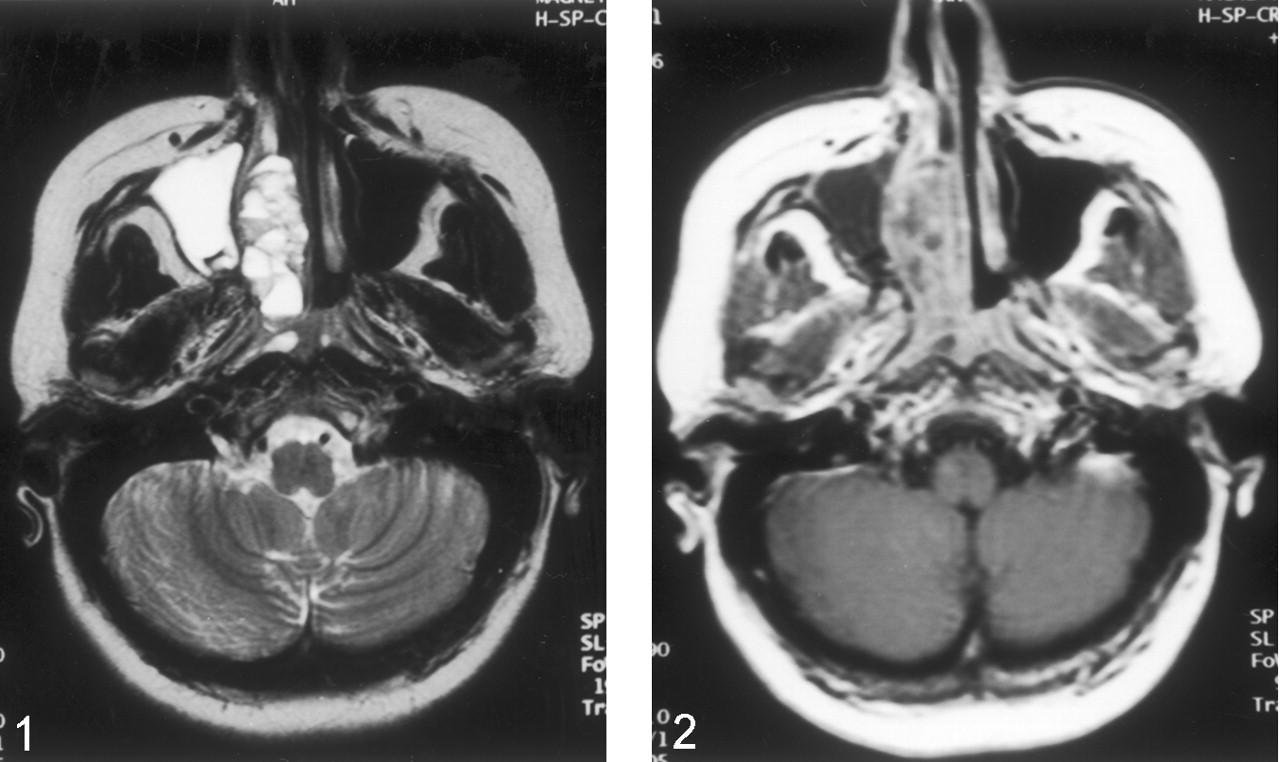

MR examination was performed with a 1.5-T MR unit (Magnetom Vision; Siemens Medical Systems, Erlangen, Germany). T1-weighted spin-echo images (TR/TE, 635/14) and T2-weighted turbo spin-echo images (5000/99) were obtained in the coronal and axial planes (Fig 1). A lobulated mass involving the right nasal cavity and ethmoid sinus extended toward the right maxillary sinus laterally and to the periorbital area superolaterally. The mass caused compression of the right optic nerve and extended to the right torus tubarius posteriorly. The lesion also extended into the anterior cranial fossa. On T1-weighted images, the mass was isointense to hyperintense relative to the neighboring skeletal muscles. On T2-weighted images, the lesion was mainly hyperintense, with fluid-fluid levels in its nasal component. After the administration of IV contrast material (Gadolinium dimeglumine, 0.1 mmol/kg), the periphery and septa of the lesions were enhancing (Fig 2).

Transverse gadolinium-enhanced T1-weighted MR image reveals enhancement of the periphery and septa of the mass.